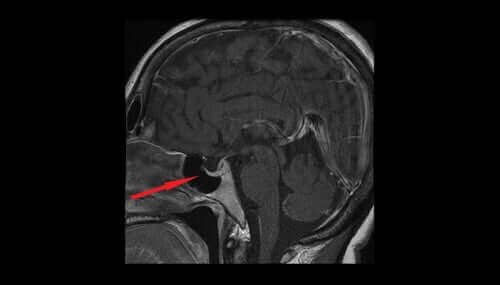

فازوبرسين أو الهرمون المضاد لإدرار البول ينبع من النواة الوطائية. من هناك، يمر إلى الفص النخامي العصبي، ثم يصل أخيرًا إلى مجرى الدم.